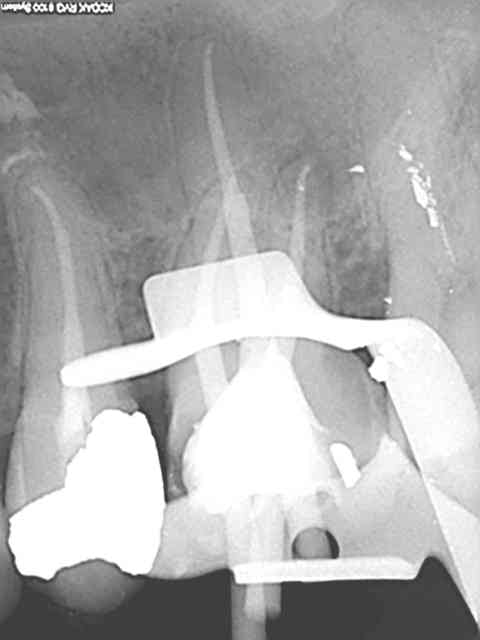

Quand je chope le mv2 qui m'avait échappé la semaine suivante.